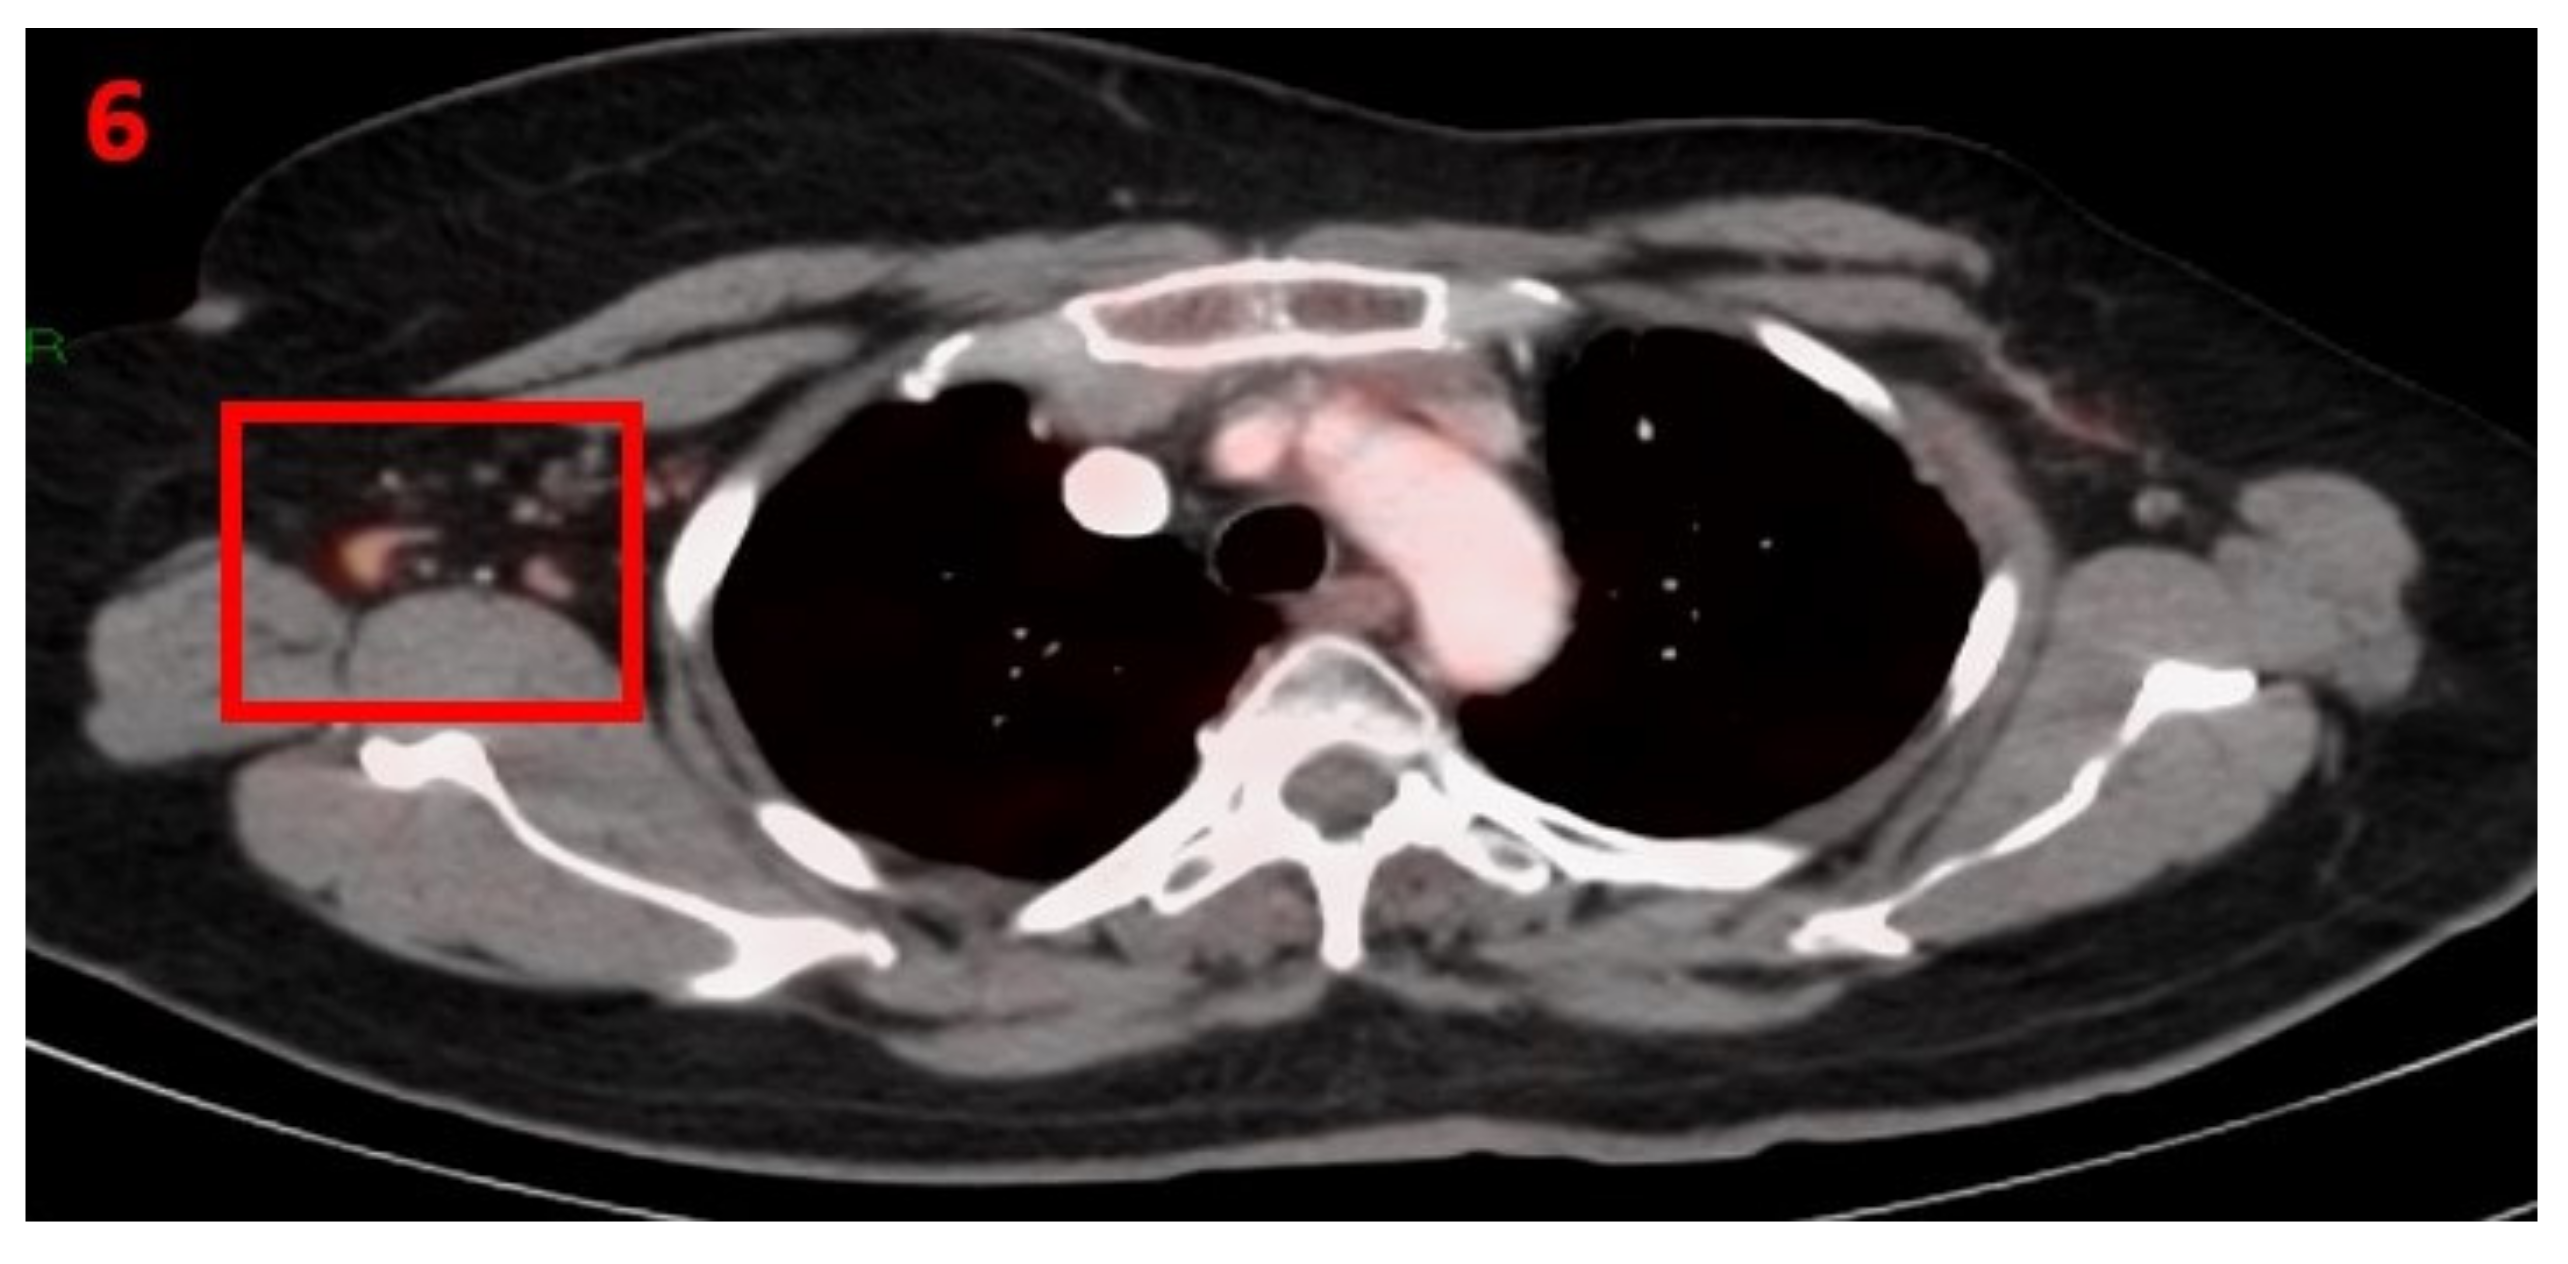

3.6. Case No 6

| Case no.6 | Breast cancer | Right arm | 8 days | Hypermetabolic uptake in the right axillary region and lymphadenopathy | Second vaccine | 10 mm | 3 | Pfizer-BioNTech |